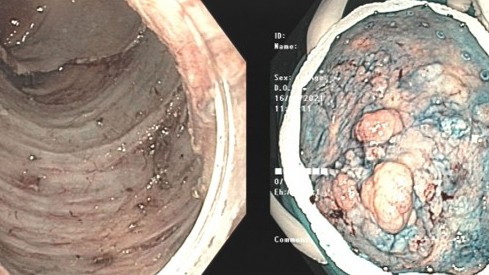

Dấu hiệu phổ biến giúp người phụ nữ phát hiện sớm ung thư trực tràng

Bệnh ung thư -  22/03/2021

Bà Lê Thị Bắc, 66 tuổi ở Thanh Hoá đến Bệnh viện Bãi Cháy, Quảng Ninh thăm khám do thường xuyên thấy đau bụng từng cơn vùng hố chậu trái và hạ vị, kèm...